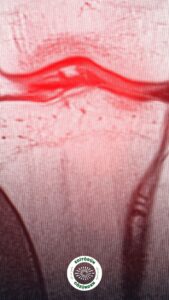

Menisküs Yırtığı Nedir? Diz İçindeki “C” Şeklindeki Koruyucu Yapı

Her iki dizde, uyluk kemiği ile kaval kemiği arasında yer alan ve “C” şeklinde olan iki adet kıkırdak yapı menisküs olarak adlandırılıyor. Bu yapılar, vücut ağırlığını dengeli şekilde dağıtarak eklem üzerindeki baskıyı azaltıyor ve ani hareketlerde dizin stabil kalmasına yardımcı oluyor.